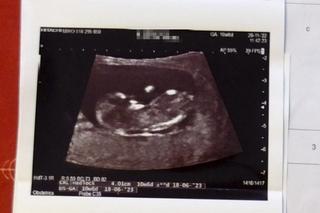

- Zaproponowano żonie tabletkę wczesnoporonnną, zdecydowanie odmówiła - dodaje Tomasz Sikora. - Na szczęście, ponieważ po południu tego samego dnia zjawił się u żony dr Suleiman i po kolejnym badaniu potwierdził to co już mówił: dziecko żyje i ma się dobrze. Trzeciego dnia pani Paulina wyszła ze szpitala. Wtedy też dostała SMS od lekarki, która jako pierwsza wydała błędną diagnozę: - Przepraszam, że niepokoję, ale przeanalizowałam pani obraz USG i taki bałagan w macicy może być po implantacji zarodka i dr Suleiman może mieć rację, że to wczesna ciąża, proszę być dobrej myśli..- napisała. Tylko tyle... Po namyśle Sikorowie postanowili poinformować o wszystkim dyrekcję szpitala i Izbę Lekarską w Lublinie.

- W naszej sytuacji mogą znaleźć się inne pary, którym nie zdoła pomóc dr Suleiman... Prawda jest taka, że mogło dojść do aborcji żywego dziecka, w szpitalu, zgodnie z prawem - mówi mężczyzna. Ostatnie badania pokazują, że dziecko rozwija się dobrze i zgodnie z planem ma przyjść na świat w czerwcu.